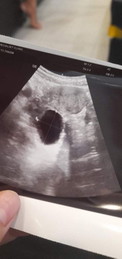

สอบถามหน่อยค่ะ ประจำเดือนมาล่าสุด 26 พ.ย 21 แล้วซื้อที่ตรวจมาตรวจ พอขึ้นสองขีดเลยตัดสินใจไปหาหม อ แต่พอซาวไม่เจอน้องเลยค่ะเจอแต่ก้อนซีส แอบกังวลค่ะคุณแม่มีใครเจอแบบเดียวกันบ้างคะ

หมอนัดตรวจอีกครั้งใช่ไหมคะ